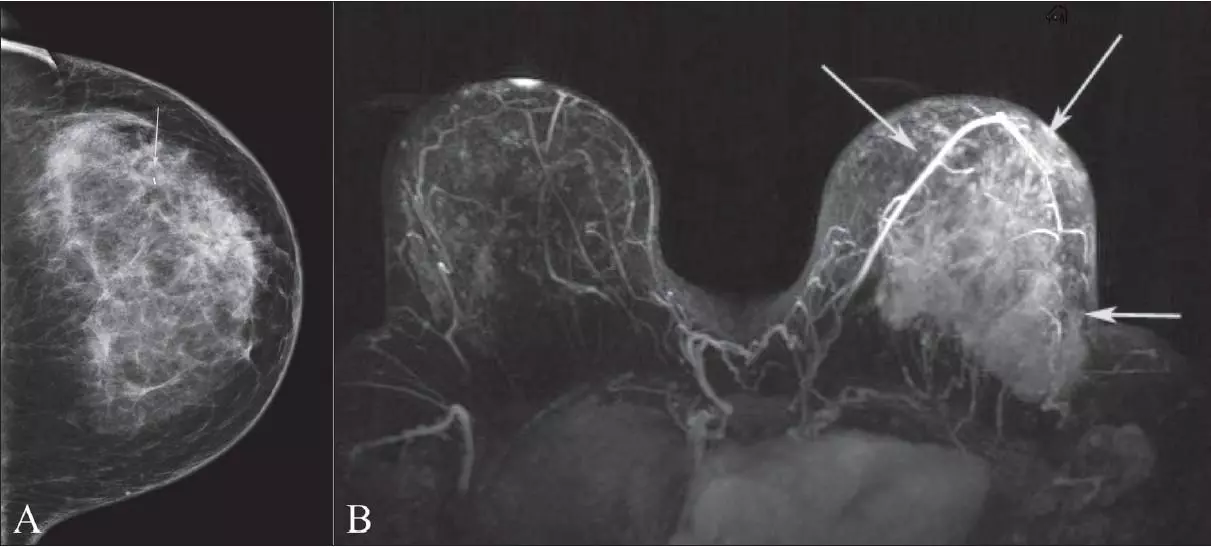

Гепатомегалия. Симптомы гепатомегалии. Умеренное увеличение печени. Умеренная гепатомегалия. Маммография косая проекция укладка. Маммография молочных желез. Маммография это исследование. Рентгеновская маммография.

Маммография косая проекция укладка. Маммография молочных желез. Маммография это исследование. Рентгеновская маммография. Подчелюстная слюнная железа на рентгене. Сиалография слюнных желез. Рентгенография слюнных желез. Контрастная сиалография слюнных желез.

Нейроэндоскопия головного мозга. Хирургическая операция на головном мозге. Эндоскопические операции на головном мозге. Хирургическое вмешательство в мозг. Магнито-резонансная томография молочной железы. Маммография дуктография. Фиброаденома молочной железы кт. Опухоль молочной железы мрт.

Магнито-резонансная томография молочной железы. Маммография дуктография. Фиброаденома молочной железы кт. Опухоль молочной железы мрт. Кт мрт томограммы легких. Кт МВС без контрастирования. Опухоль легкого на кт с контрастированием. Кт естественное контрастирование.

Опухоль печени доброкачественная кт. Первичные злокачественные опухоли печени. Злокачественные новообразования печени кт. Первичные и Метастатические опухоли печени. Маммография. Маммограмма молочных желез. Маммография после 40 лет проводится.

Маммография. Маммограмма молочных желез. Маммография после 40 лет проводится. Виды роста злокачественных опухолей. Рост злокачественных новообразований. Злокачественные опухоли характеризуются. Форма злокачественной опухоли.

Метастатическое поражение печени. Метастатические опухоли печени. Злокачественные образования печени. Молочная железа маммография. Мастопатия на маммографии. Опухоль молочной железы маммограмма. Рик молочной железы маммографич.

Молочная железа маммография. Мастопатия на маммографии. Опухоль молочной железы маммограмма. Рик молочной железы маммографич. Опухоль головного мозга симптомы. Новообразование в головном мозге. Раковые заболевания головного мозга. Объемное образование головного мозга.

Терминальная стадия онкологии. Опухоль грудной стенки кт. Опухоль в терминальной стадии. Маммография молочных желез объемное образование. Опухоль молочной железы. Онкология молочной железы. Опухольмолочныйжелезы.

Маммография молочных желез объемное образование. Опухоль молочной железы. Онкология молочной железы. Опухольмолочныйжелезы. Доброкачественная злокачественная опухоль головного мозга мрт. Глиома головного мозга мрт. Опухоль головного мозга на кт.